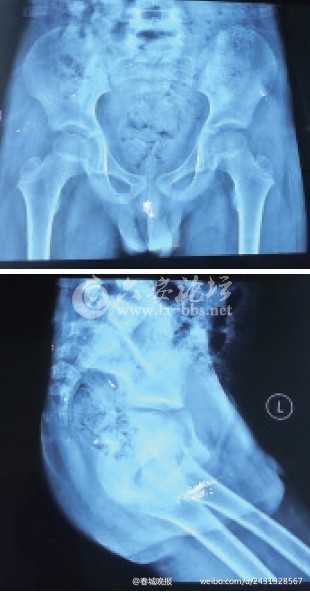

江女士介绍,今年年初发现孩子身上起脓包,还以为是普通皮肤病,了解病情后,带着孩子四处诊治无果,甚至曾一度绝望。

奇奇60多岁的爷爷于迪(化名)介绍,大约两年前,他和老伴发现孙子排出的粪便里有水银,之后带奇奇去昆明市儿童医院检查,医生说,水银已通过粪便排出了孩子体外,没事了。

去年11月,家人发现奇奇臀部左右两侧各起了两个大包,于迪用手指圈起来一个一元硬币大小的圈,“肿起来一两厘米高。”

于迪说,孙子刚开始不怎么喊痛,后来肿块越来越大,痛得坐不住,玩电脑都是跪着。

直到今年二月份,儿子和儿媳妇挤破这些肿块,发现里面流出来的不是脓血,而是亮晶晶的水银。

家人带着孩子辗转求医,最后送入北京解放军307医院治疗。

今年2月,昆明男童奇奇(化名)体内被检出汞含量严重超标,其中血汞和尿汞含量分别超标200多倍和1万多倍。事件经曝光后,引起极大关注。昨天记者从昆明市公安局有关部门获悉,目前一名男性犯罪嫌疑人已被检察机关批捕,具体案情仍在进一步调查。